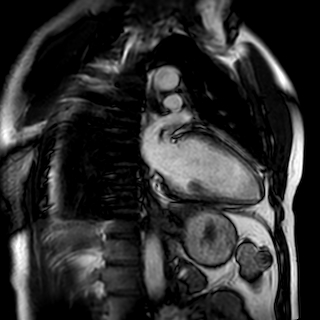

冠脉磁共振:给心脏和血管做 “全方位无创体检”

冠脉磁共振是利用磁场和无线电波成像的先进技术,无需插管、无电离辐射,既能清晰呈现冠状动脉的完整形态,又能同步评估心脏功能,相当于一次完成 “血管解剖 + 心肌功能” 的双重检查。

✅ 对血管:可精准识别冠状动脉主干及分支的狭窄程度、斑块性质(尤其是易破裂的危险斑块),还能发现先天性冠脉畸形、心肌桥等血管结构异常,就像给血管装了 “高清放大镜”,连血管壁的细微病变都无处遁形;

✅ 对心脏:能动态捕捉心脏跳动全过程,评估心肌缺血范围、梗死疤痕、心肌纤维化程度,还可精确计算心脏泵血功能,判断心肌肥厚、心脏扩大等结构问题,为心肌病、心肌炎等疾病诊断提供关键依据。